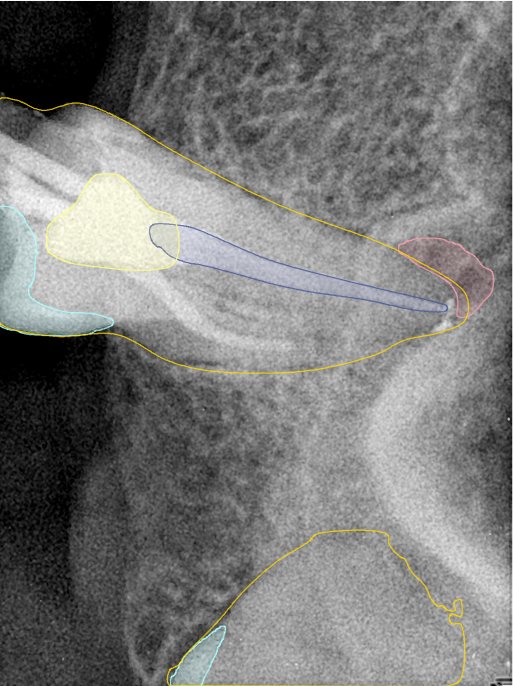

CR/DR 牙齿分割阶段记录

当前进展

- 完成了 CR/DR 牙齿相关分割训练

- 当前结果已经达到阶段预期,但仍有细节问题需要继续处理

相关测试

遇到的问题

- 训练过程中出现过 mask 下移问题

- 部分结果会出现 box 填充异常

- mask 边缘仍然有比较明显的锯齿感

第二版算法问题测试

| 第一版 | 第二版 | 是否解决 | |

|---|---|---|---|

![]() | ![]() ![]() 边角识别有问题 龋齿识别不全 牙髓识别不全 | ![]() | 解决 |

![]() | ![]() 边角识别有问题 识别信息有误 自查(牙冠识别不全) | ![]() | 解决 |

![]() | ![]() ![]() 边角识别有误 大范围填充识别遗漏 | ![]() | 解决 |

![]() | ![]() 识别信息不全 | ![]() | 解决 |

![]() | ![]() ![]() 边角问题 牙胶识别不全 牙冠识别不全 | ![]() | 解决 |

![]() 换图片 | ![]() | ![]() 牙冠部分稍微白了一些就识别成小范围修补,部分判断异常 | 部分解决,修复类略敏感,牙冠部分稍微白了一些就识别成小范围修补,部分判断异常。 |

![]() | ![]() ![]() 牙冠识别不全 牙髓不全 根尖炎龋齿识别有误 | ![]() | 解决 |

![]() | ![]() | ![]() | 解决 |

![]() 换图片 | ![]() | ![]() | 解决 |

![]() | ![]() 牙冠识别有误 | ![]() | 解决 |

![]() 换图片 | ![]() ![]() 边角识别有误 | ![]() 修复类敏感 | 部分解决,图像过白,导致修复类判断异常。 |

![]() 换图片 | ![]() 牙冠识别不全 | ![]() 修复类敏感 | 部分解决,图像过白,导致修复类判断异常 |

结论:修复类出现了不鲁棒的情况,后续需要加入轮廓的扩充数据进行增强。